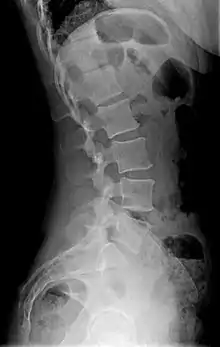

Diagram showing normal curvature (posterior concavity) of the cervical (neck) and lumbar (lower back) vertebral column (spine) | |

Lordosis is historically defined as an abnormal inward curvature of the lumbar spine.[1][2] However, the terms lordosis and lordotic are also used to refer to the normal inward curvature of the lumbar and cervical regions of the human spine.[3][4] Similarly, kyphosis historically refers to abnormal convex curvature of the spine. The normal outward (convex) curvature in the thoracic and sacral regions is also termed kyphosis or kyphotic. The term comes from the Greek lordōsis, from lordos ("bent backward").[5]

Precise diagnosis is done by looking at a complete medical history, physical examination, and other tests of the patient. X-rays are used to measure the lumbar curvature. On a lateral X-ray, a normal range of the lordotic curvature of between 20° and 60° has been proposed by Stagnara et al., as measured from the inferior endplate of T12 to the inferior endplate of L5.[18] The Scoliosis Research Society has proposed a range of 40° and 60° as measured between the upper endplate of Th12 and the upper endplate of S1.[18] Individual studies, although using other reference points, have found normal ranges up to approximately 85°.[18] It is generally more pronounced in females.[18] It is relatively constant through adolescence and young adulthood, but decreases in the elderly.[18]